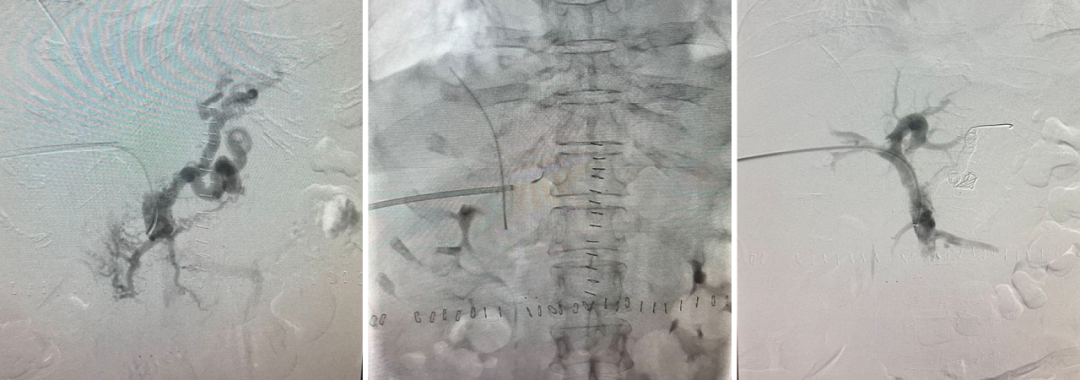

布加综合征(BCS)

对肝静脉闭塞型,直接穿刺下腔静脉建立 DIPS 通道;

对下腔静脉+肝静脉联合闭塞,先置入下腔静脉支架,再通过其作为“桥梁”完成 TIPS;

曾有一例19岁少女,每日需放腹水2000ml,术后当天腹水完全消退,疗效极为显著。

DIPSS-肝静脉闭塞(XJD)

肝静脉闭塞型

下腔静脉型合并消化道出血

下腔静脉型

栓塞材料与再干预技术

栓塞剂从早期的泡沫硬化剂、无水酒精、弹簧圈,发展到如今的生物组织胶,止血更彻底;

泡沫硬化剂—无水酒精—弹簧圈—生物组织胶

针对分流道再狭窄或再出血,创新应用平行支架技术,并通过体外模拟验证支架扩张可行性;

平行支架技术

TIPS术后再出血,胃底静脉栓塞+平行支架

经皮经肝导丝引导穿刺门静脉左支,血管塞栓塞异常分流道及胃底曲张静脉

弹簧圈联合血管塞+组织胶栓塞异常分流道